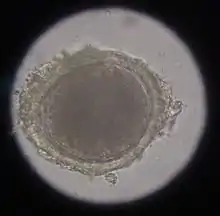

Microscopic image of an egg packet of the cucumber nematode tapeworm.

The cucumber tapeworm (dipylidium caninum) - named after its limbs resembling a cucumber seed - is up to 80 cm long and parasitizes in the anterior small intestine. The obligate intermediate host is primarily the cat flea, occasionally also the cat hair flea. The tapeworm members shed in the intestine leave the anus with the feces or by active migration. The eggs are ingested by the larvae of the insects, penetrate their intestinal wall and develop in the fat body to the fin stage (cysticercoid). Depending on the external temperature, the cysticercoid is infectious as soon as the adult flea hatches or several days later. Infection occurs by eating the fleas, whereupon the fin grows into the adult tapeworm in the small intestine. The prepatency period is about three weeks.

Infestation with cucumber nematode tapeworm can be determined by detecting the limbs in the anal region or by detecting the 35-53 µm eggs or egg packets in the feces using flotation methods. However, these detection methods are very uncertain. In one study, autopsies revealed an infestation rate of 34.5%, even though all previous fecal examinations were negative.[10]